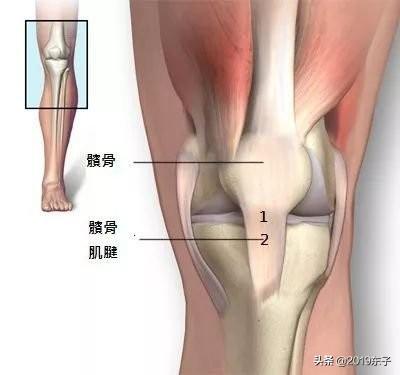

筋肉は骨を守る「鋼鉄のケーブル」である。筋肉は力を失い、骨には過負荷がかかる。筋肉が力を失うと、骨に過負荷がかかり、特に以下のような多くの問題をもたらすことになる。膝関節のように重い骨にとって、脚の筋肉の強さは非常に重要である。。

上の図では、筋肉と腱が協力して膝関節を保護していることがわかる。一般的に言って膝から上のこの2つの筋肉が著しく縮むことは、膝の問題とは程遠い。